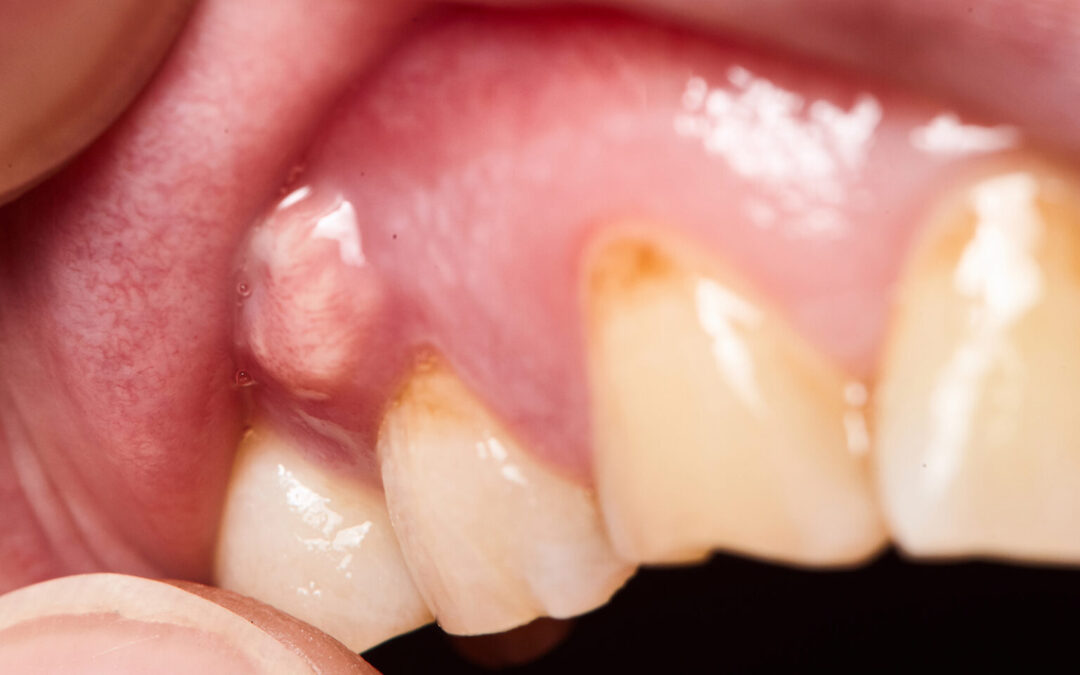

In more severe cases, individuals may experience fever, swollen lymph nodes in the neck or jaw, or difficulty opening the mouth. Sometimes, a visible bump or pimple-like swelling appears on the gum, which may rupture and release pus. While this might provide temporary relief, it does not mean the infection has healed. All symptoms of an abscess, whether mild or severe, warrant professional evaluation to prevent the spread of infection and systemic complications.